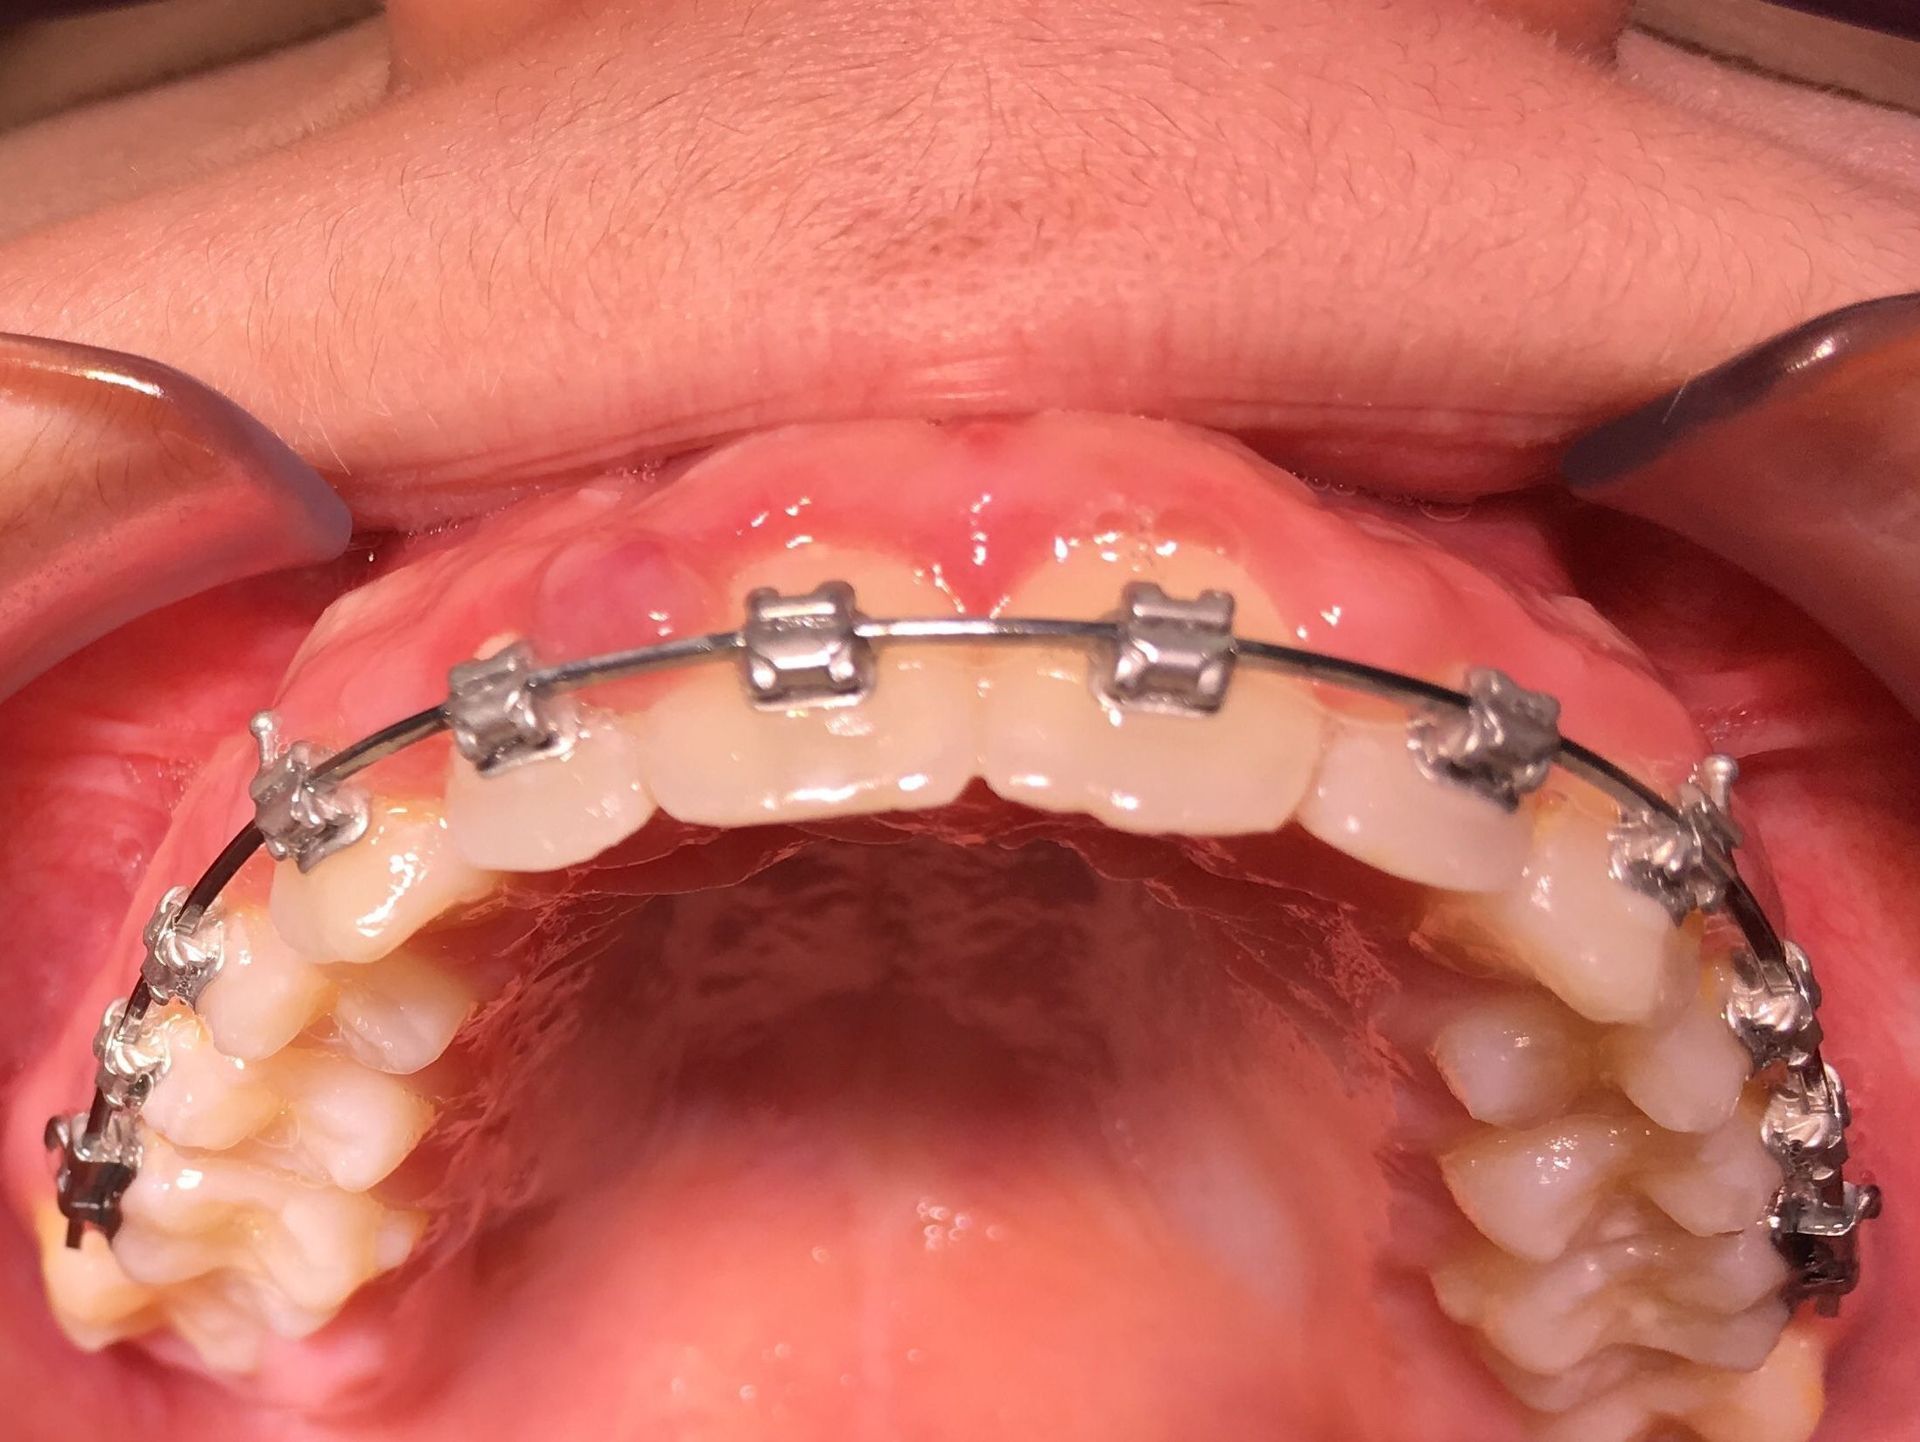

Avant et après greffe de gencive